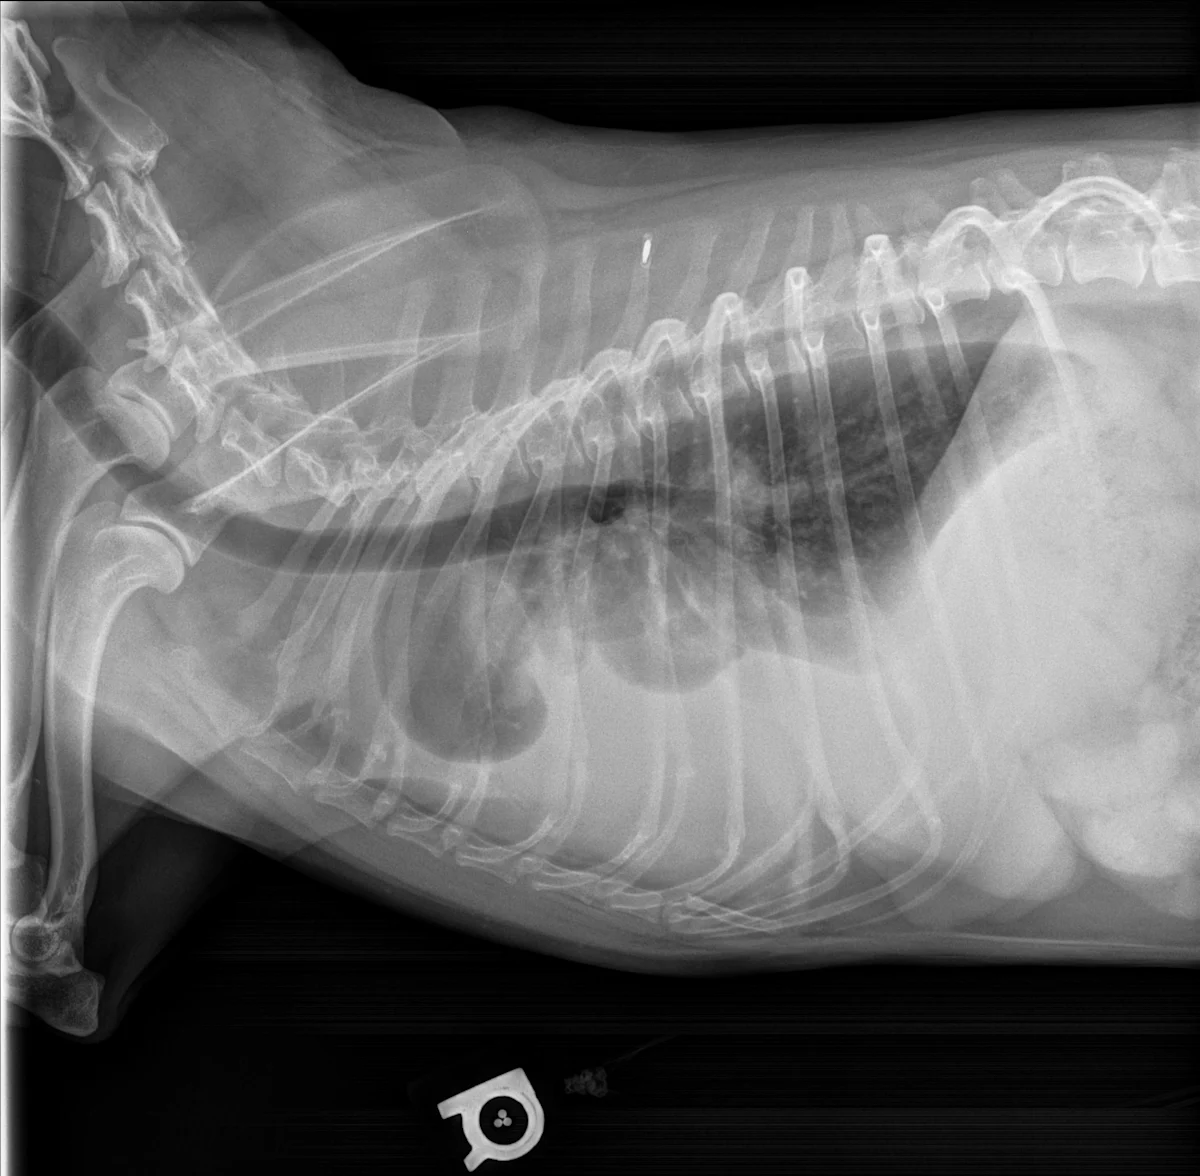

Pleural effusion can be easily identified on radiographs (Figures 1 and 2) and ultrasound (Figure 3). In patients with respiratory distress, oxygen and sedation should be administered before standard aseptic, often ultrasound-guided, thoracocentesis is performed. Removal and collection of fluid can quickly improve oxygenation and ventilation and allow clinical investigation to determine the cause of effusion.

Thoracic ultrasound of the left side of the chest in a dog with marked pleural effusion